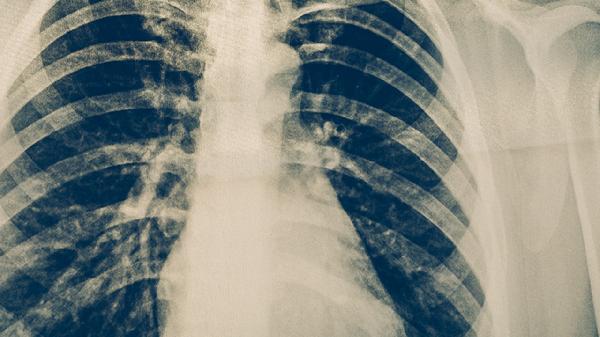

寻常型间质性肺炎是一种慢性进行性肺间质疾病,主要特征为肺泡壁炎症和纤维化。病因包括环境暴露、自身免疫异常、遗传因素、药物反应及特发性因素,临床表现为进行性呼吸困难、干咳和双肺底爆裂音。

多数寻常型间质性肺炎属于特发性肺纤维化,可能与衰老相关细胞异常有关。这类患者肺功能呈进行性下降,需定期评估氧合指标,终末期考虑肺移植。